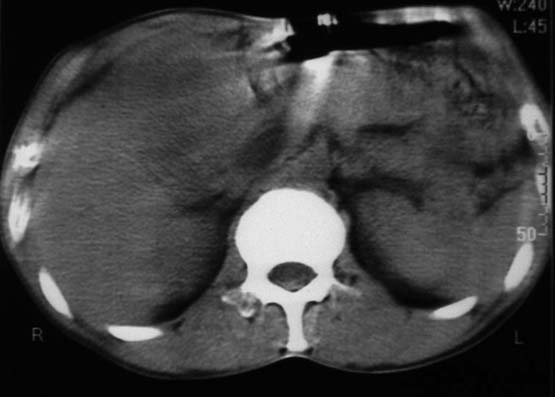

男,50y,右上腹包块痛10天,查:右上腹饱满,右肋下触及6*6cm大小包块,质硬,压痛。患者诉:10天前感冒胸闷,痛,后痛及右上腹部,既往有肝炎病史。

没有增强!只能考虑左叶内侧段巨块型肝癌(外生型)可能性大;胆囊呢?不除外胆囊癌累及肝脏。

病变位于胆囊窝内,其内密度不均,肝总管及胆总管扩张,胃里面没有清水充盈,不解为什么楼主不做好了准备再做呢,支持:“左叶内侧段巨块型肝癌(外生型)可能性大;不除外胆囊癌累及肝脏”建议增强吧。

考虑:肝左内叶巨块型癌,主动脉旁淋巴结转移.(有一层面似见胆囊受压.)

患者做完之后就走了,不愿做增强,也无法追踪病史真是抱歉。